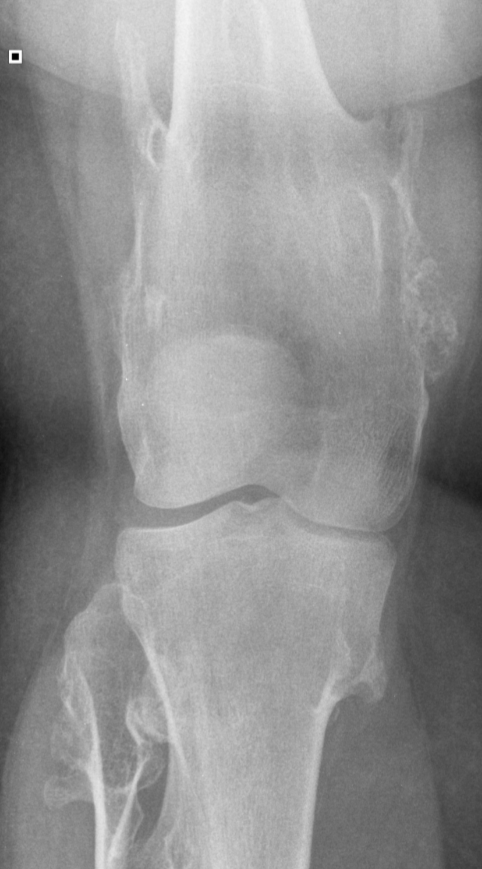

3. Diaphyseal Aclasis